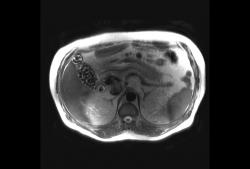

Через 5 дней повторное УЗИ.

Изображение

Внутренние структуры однородные. Отмечается некоторое утолщение стенки пузыря.

Первым делом надо исключать острый гепатит, утолщённые слоистые стенки пузыря с "облитерацией просвета" (в отличие от острого холецистита, когда просвет сохраняется); очень частая (и кстати, обратимая) находка на ранних стадиях острых гепатитов.